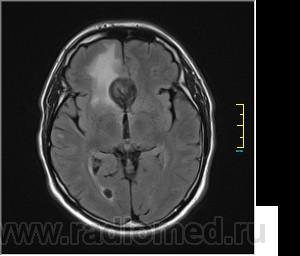

Ax T2 Flair:

Иначе говоря, аневризма с хронической геморрагией, т.к. мы видим фракции крови различного возраста.

Постепенное пристеночное образование тромбов приводит к появлению типичного для аневризмы феномена -слоистости МР сигнала в полости аневризмы. Данная картина демонстрирует слоистый характер тромботических масс в полости аневризмы .Функционрирующая часть имеет низкий сигнал во всех режимах сканирования. Дополнительно-перифокальный отек.

А может более корректно интерпретировать как частично тромбированная аневризма... Уж коь речь идет о фракциях, ну то есть о тромбе по сути.... Ну и плюс перфокальный отек головного мозга (вероятнее цитотоксический+вазогенный).